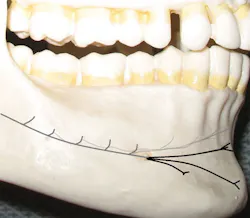

The inferior alveolar nerve, which travels through the mandibular canal, bifurcates just posterior to the mental foramen (see Figures 1, 2) to become the incisive nerve (continues to the midline through the mandibular canal) and the mental nerve (exits at the foramen and courses outside the bone toward the midline). When we provide a mandibular block, both nerves are anesthetized.

The incisive and mental nerves should not be confused. The incisive nerve innervates the pulps of the teeth anterior to the mental foramen, usually the premolars through the centrals on one side. The mental nerve innervates the skin of the chin, lower lip, and facial soft tissues anterior to the mental foramen on one side.

Figure 1: Abbreviated illustration of pathway: Incisive nerve (grays), mental nerve (black)